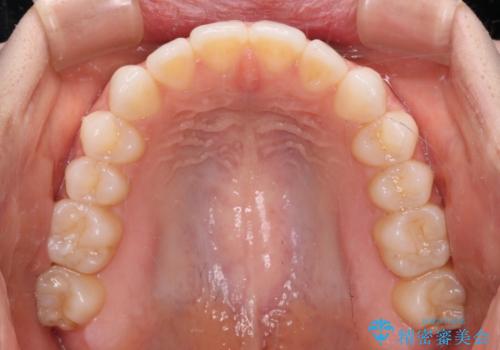

上下前歯が接触しない オープンバイトをインビザラインで改善

- 前歯の上下スペースによる食べにくさを気にして来院された患者様です。

インビザラインにより上下の前歯の隙間を閉じていくこととしました。

上下の奥歯を圧下させるようにすることで、前歯を接触させるように計画しました。

上下の隙間に舌が入り込むことがオープンバイトの原因であったため、舌の筋肉のトレーニングも並行して行い、後戻りの抑制を図りました。